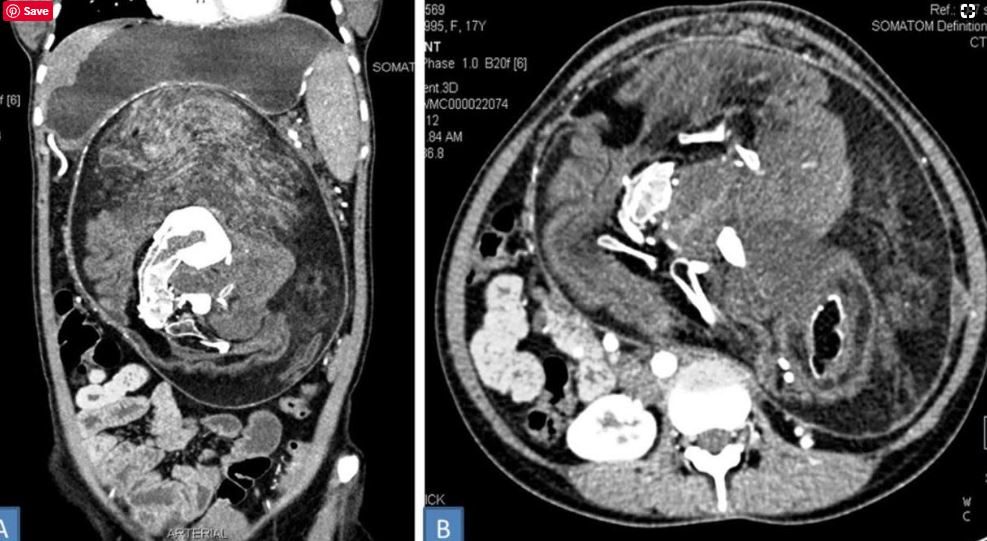

في الفحص البدني الأولي، اشتبه في الانتفاخ أنه ورم، وهو إلى حد ما كان كذلك فعلاً. ولكن عندما أجروا تصويراً مقطعياً مُحوسَباً للانتفاخ، وجدوا رواسب من الكالسيوم تبدو “على شكل فقرات وضلوع وعظام طويلة”، لتكشف الحقيقة المروعة في نهاية المطاف. بعدها بدأ الأطباء في العمل على إزالة الجنين.

وبحسب التقرير، تتكون محتويات الورم من “الشعر وعظام مكتملة النمو وأجزاء أخرى من الجسم”. وشملت الأخيرة “عدة أسنان وهياكل تشبه براعم الأطراف”. كما أن حجم الجنين الهائل الذي بلغ طوله 36 سنتيمتراً وعرضه 16 سنتيمتراً وارتفاعه 10 سنتيمترات، أهله أن يصبح أكبر جنين وجد في حالة جنين داخل جنين لشخص بالغ.